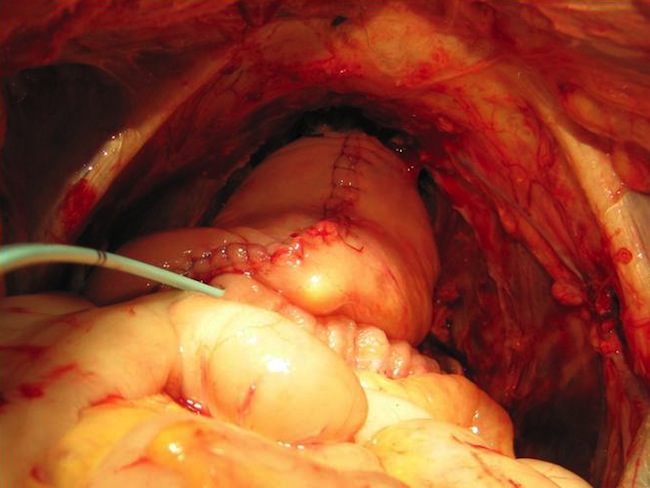

Хирургическое вмешательство во всех случаях предполагало после лапаротомии выполнение ревизии брюшной полости с уточнением местной распространенности опухоли и дополнительной оценки признаков отдаленного метастазирования. Далее мобилизовали слепую кишку, восходящий, сигмовидный и ректосигмоидный отделы ободочной кишки. Париетальную брюшину рассекали от нижнегоризонтальной ветви двенадцатиперстной кишки вдоль аортокавального промежутка, общих и наружных подвздошных сосудов.

Производили диссекцию парааортальной, межаортокавальной и паракавальной клетчатки и лимфатических коллекторов и далее по ходу общих, наружных и внутренних подвздошных сосудов, а также из запирательный ямок от перефирии к удаляемому препарату.

Затем выделяли, лигировали и пересекали нижнюю брыжеечную артерию в месте ее отхождения от аорты. Лигировали и пересекали сосуды брыжейки сигмовидной кишки и пересекали саму кишку, отступив от места ее вовлечения в опухолевый конгломерат не менее 10 см. Далее острым путем производили выделение задней и боковых стенок прямой кишки до верхушки копчика.

У мужчин выделяли, лигировали и пересекали семявыносящие протоки с обеих сторон у внутреннего кольца пахового канала. У женщин лигировали и пересекали круглые и воронкотазовые связки матки. При выполнении полных эвисцераций малого таза мобилизовали и пересекали мочеточники с обеих сторон на уровне их пересечения подвздошных сосудов. Последние интубировали мочеточниковыми катетерами типа «pig tail» №9 Schr до почечных лоханок. Далее выполняли мобилизацию мочевого пузыря со стороны верхушки, боковых и задней поверхностей со всей паравезикальной клетчаткой. Поэтапно лигировали и пересекали верхние и нижние мочепузырные артерии. У мужчин пересекали пубопростатические связки, лигировали вены Санториниевого сплетения. Уретру пересекали на уровне проксимальной границы мембранозного отдела.

При выполнении инфралеваторных эвисцераций малого таза, на промежностном этапе вмешательства выполняли окаймляющий разрез кожи промежности от верхушки копчика до корня полового члена у мужчин и до наружного отверстия уретры – у женщин. Пересекали анокопчиковую связку и мышцу, поднимающую задний проход. Препарат удаляли со стороны брюшной полости единым блоком.